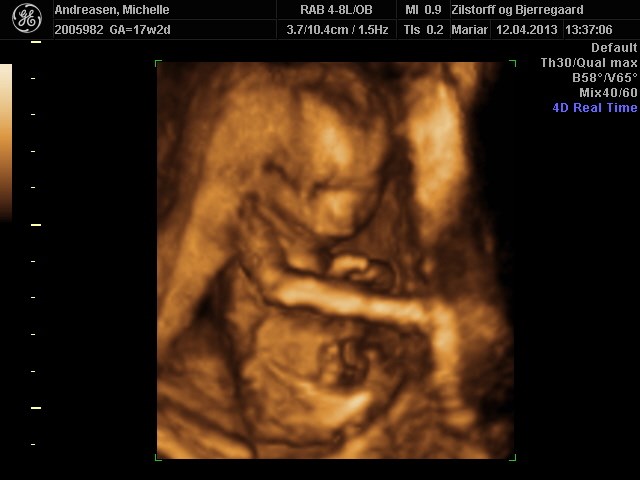

Her er nogle billeder af vores pige 17+2

Vedhæftede fotos (klik for at se i fuld størrelse)